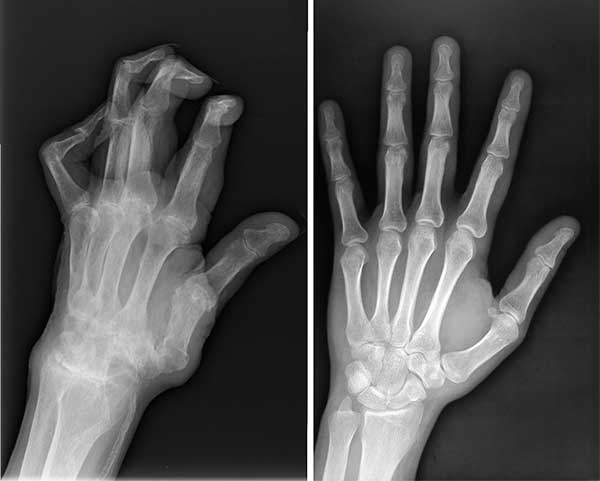

ไม่ใช่แค่หนูคนเดียวที่รอดเพราะผลิตภัณฑ์มหัศจรรย์ตัวนี้ สามีหนูป่วยเป็นโรคข้ออักเสบ ปลายนิ้วเสียหายมาก หนูเลยซื้อ Flexvits ให้เขาทาน พวกเราทานด้วยกันแล้วก็หายกันทั้งคู่เลยค่ะ

ภาพเอกซเรย์เปรียบเทียบก่อนและหลังทาน Flexvits ของสามี

ภาพเปรียบเทียบสภาพมือของสามีก่อนและหลังทาน Flexvits